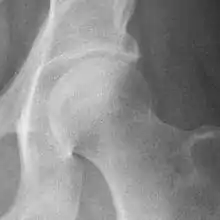

Hip

Hip joint with no signs of osteoarthritis.

The most commonly used radiographic classification system for osteoarthritis of the hip joint is the Kellgren–Lawrence system (or KL system).[6] It uses plain radiographs.

Osteoarthritis of the hip joint may also be graded by Tönnis classification. There is no consensus whether it is more or less reliable than the Kellgren-Lawrence system.[8]

Severe (Tönnis grade 3) osteoarthritis of the hip.

Tönnis classification[9]

Grade Description

0No osteoarthritis signs

1Mild:

• increased osteosclerosis

• minor joint space narrowing (normal joint space is at least 2 mm at the superior acetabulum)[7]

• no or minor loss of head sphericity

2Moderate:

• small bone cyst

• moderate joint space narrowing

• moderate loss of head sphericity

3Severe:

• large bone cysts

• severe joint space narrowing, or joint space obliteration

• severe deformity of the head